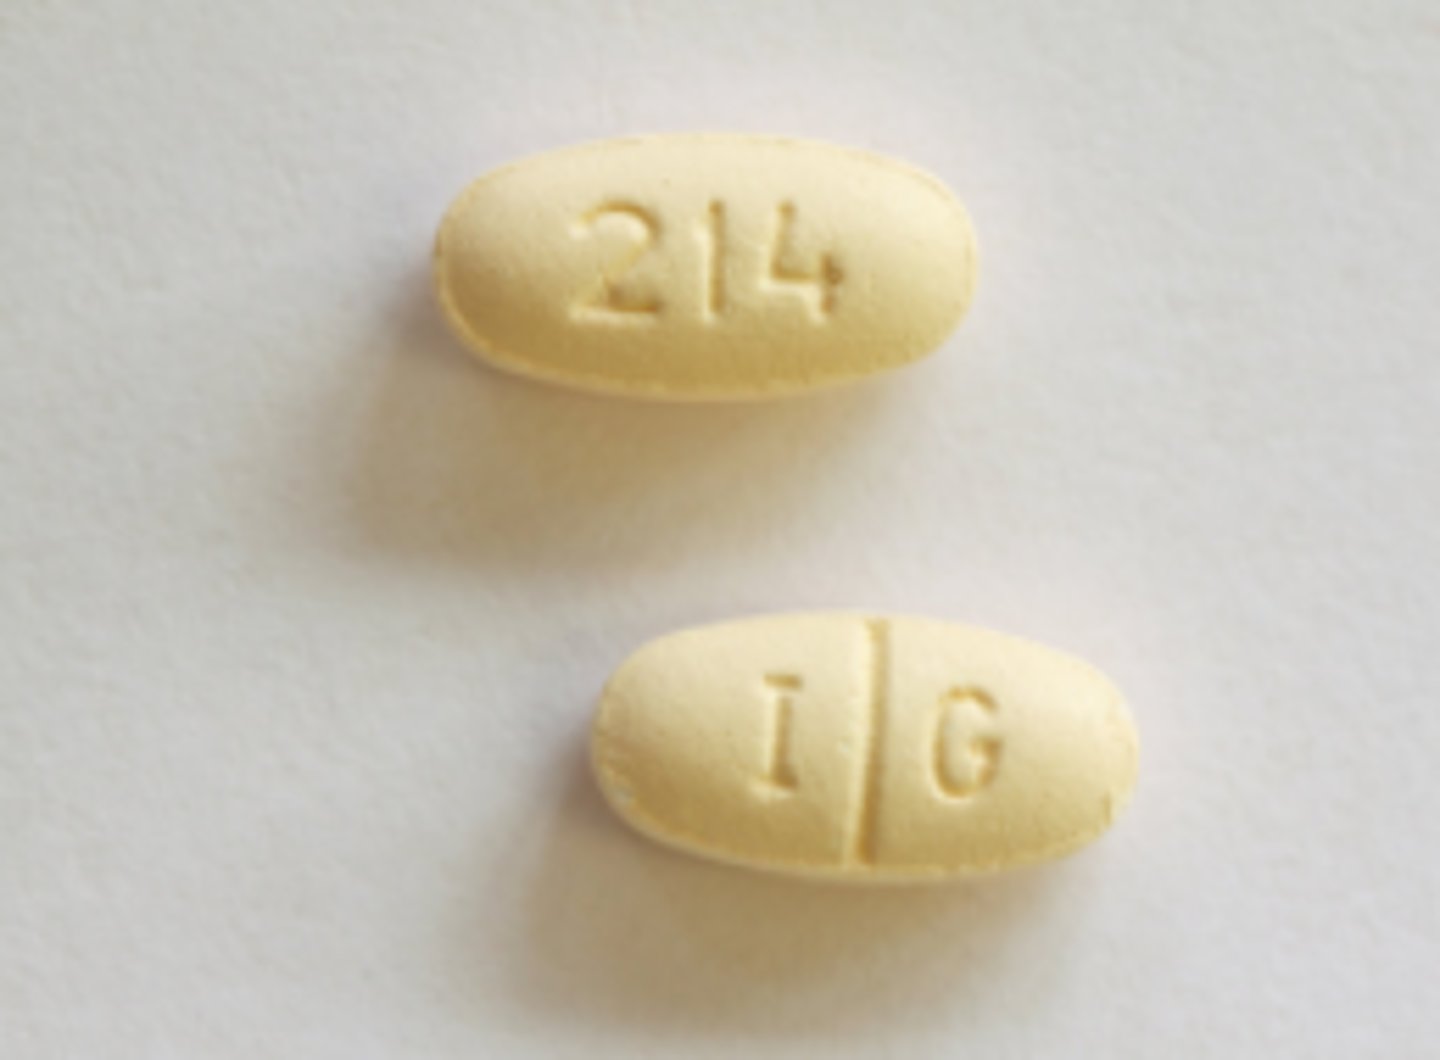

Metformin

Brand: Glucophage

Class: Biguanide

Indication: Diabetes medication

Schedule: NCLM